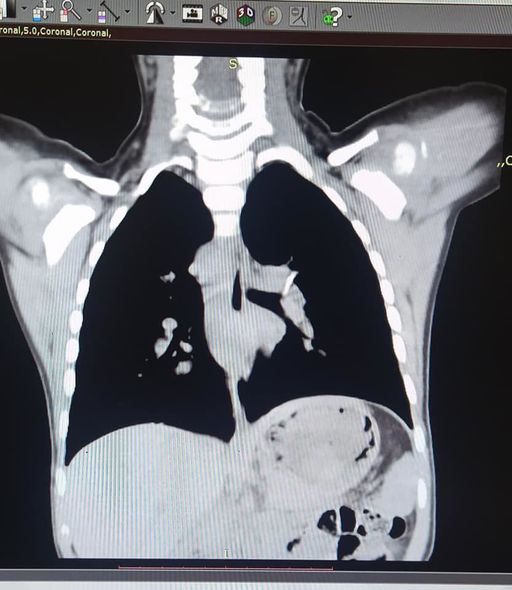

“Artıq çətinliklə nəfəs alırdı, xırıltı uzaqdan eşidilirdi. Körpənin bir yaşı olanda balıq yediyini deyirlər və ondan sonra qızdırma öskürək, xırıltı başlayıb. Aparılan bütün müalicələrə baxmayaraq xırıltı, öskürək getdikcə artırdı və tez-tez temperaturu yüksəlirdi. Valideynləri vəziyyətinin getdikcə pisləşdiyini və vəziyyətinin ağırlığı ilə əlaqədar müraciət etdikləri klinikalarda qəbul etmədikləri üçün bizim klinikaya müraciət etdilər. Ciddi risk daşısa da, körpənin rahat nəfəs alması üçün sümüyü nəfəs borusundan çıxarmaq məcburiyyətində idik. Bronxoskopiya işıqlı alətlə nəfəs borusuna girilərək çətinliklə olsa da, sol ana bronxdan sümüyü problemsiz çıxartdıq. Nəhayət ki, 1 ilin sonunda balaca qızımız rahat nəfəs almağa başladı”.